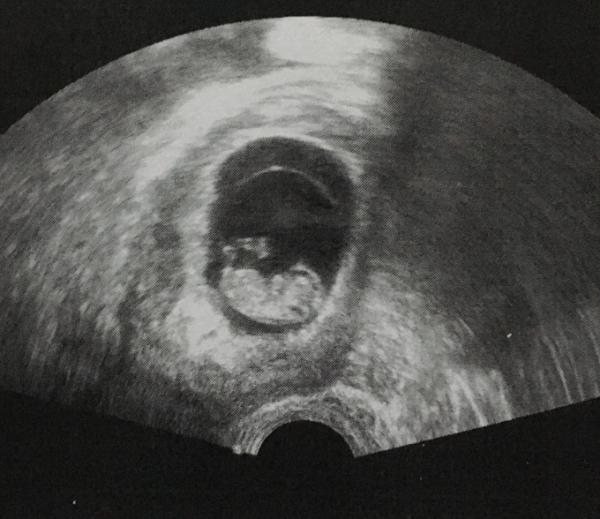

Und das andere Bild

Bild zu